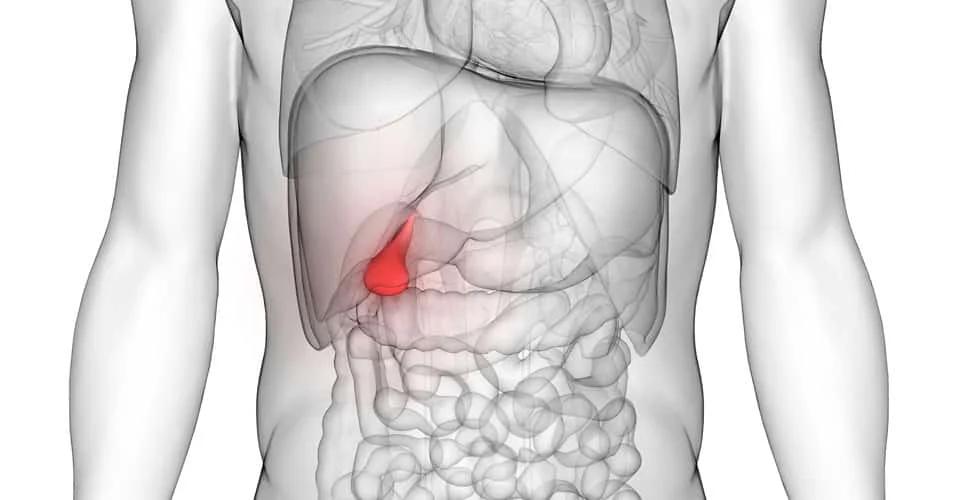

Η χοληδόχος κύστη, ένα μικρό όργανο που βρίσκεται κάτω από το ήπαρ, συνδέεται στενά με αυτό μέσω του χοληδόχου πόρου.